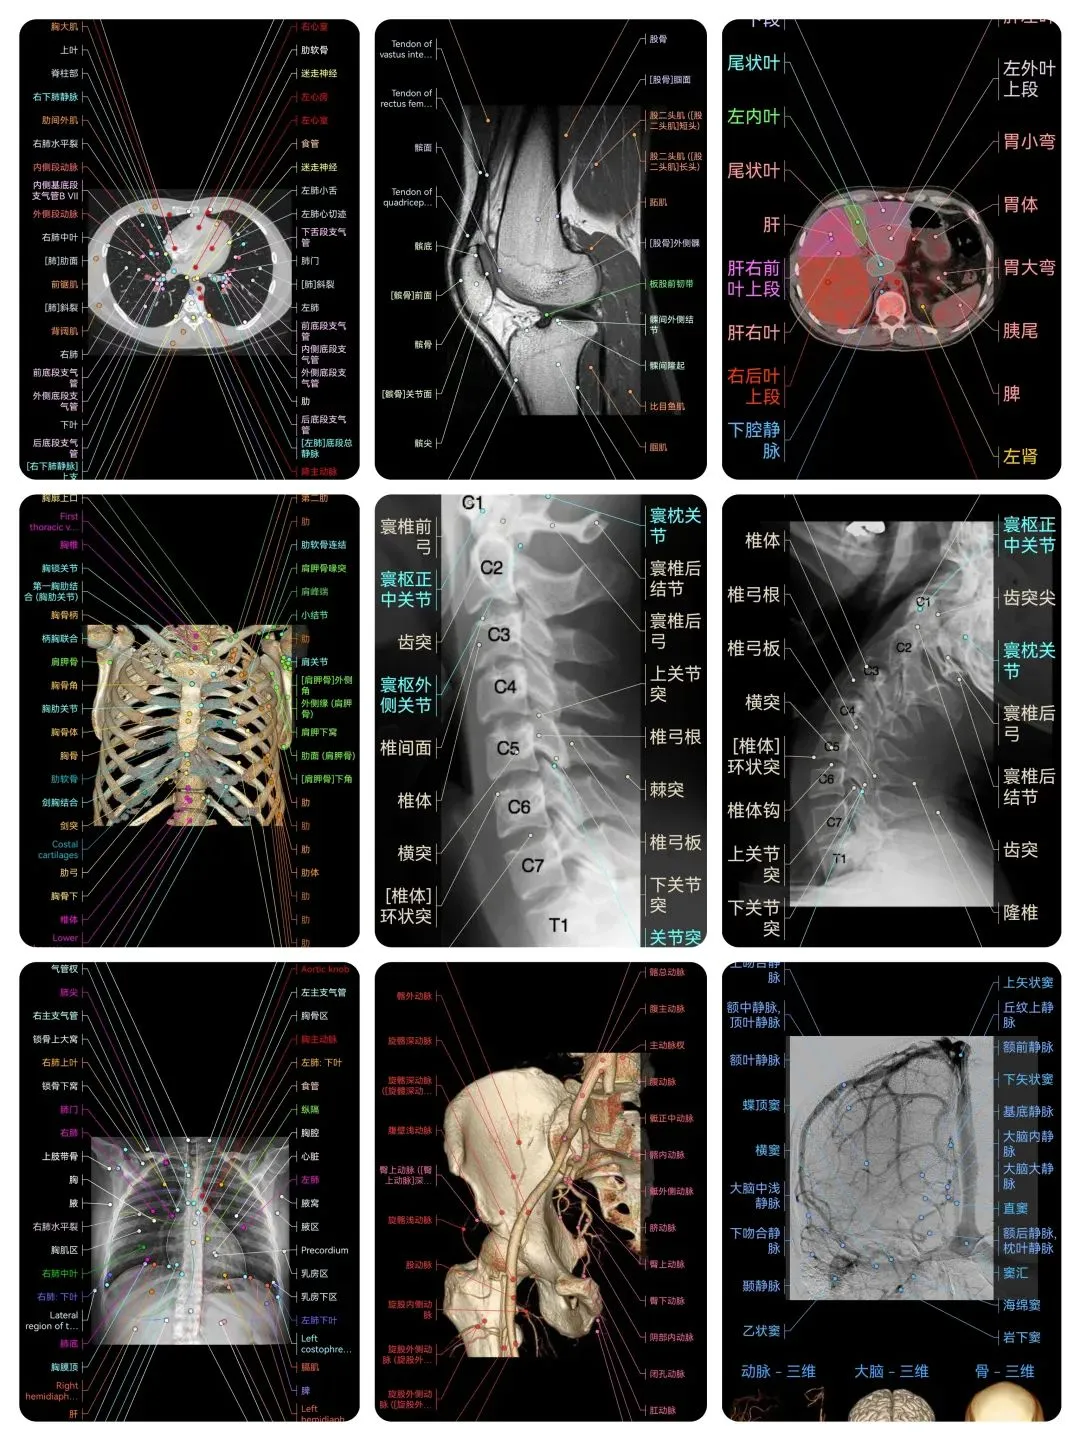

🌈这是国外引进的一款专业影像解剖学习软件。

覆盖了X光、CT、MRI、断层大体解剖、核医学、介入造影、医学插图等多个模块,覆盖全身各个系统的影像解剖(正常解剖结构,无病例),其中的解剖结构高达87万个,结构标注超精细,超高清图像,历时两年研发设计完成✅。